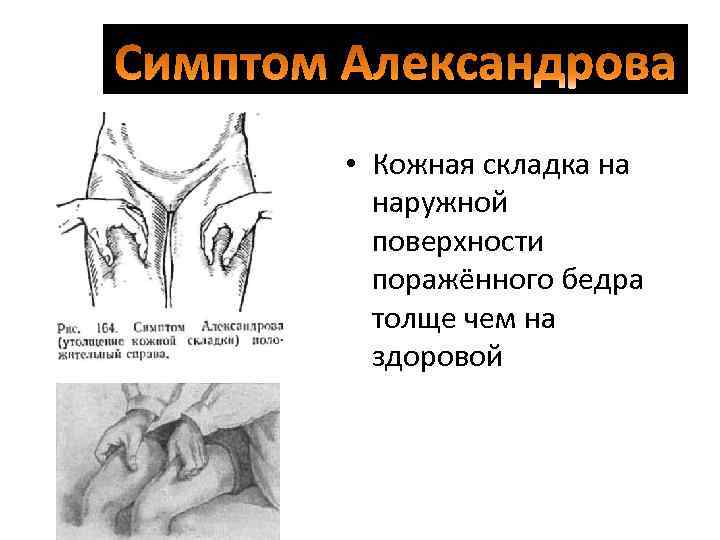

• Кожная складка на наружной поверхности поражённого бедра толще чем на здоровой

• Кожная складка на наружной поверхности поражённого бедра толще чем на здоровой